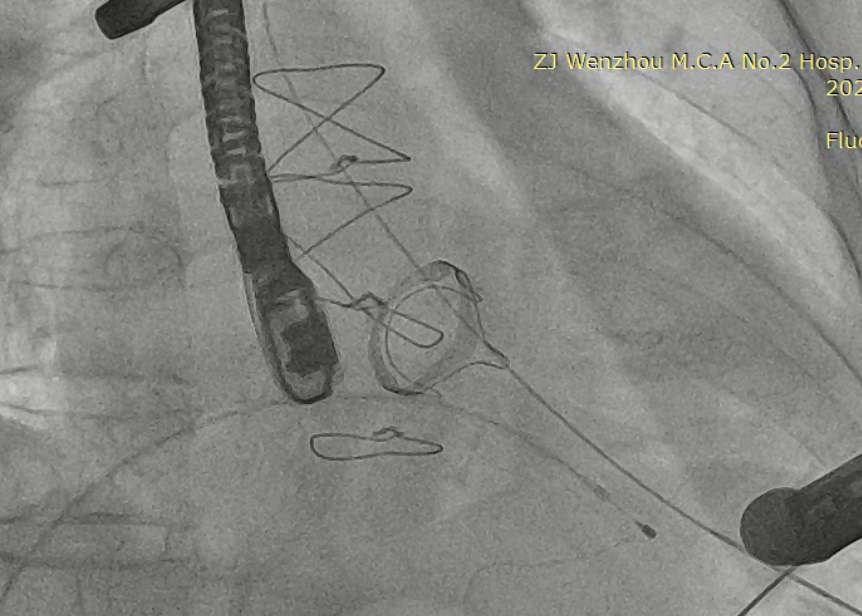

扩张鞘预扩心尖穿刺点

输送器进入左室至生物瓣下方

CDFI提示过瓣血流通畅

CDFI示少量瓣周漏